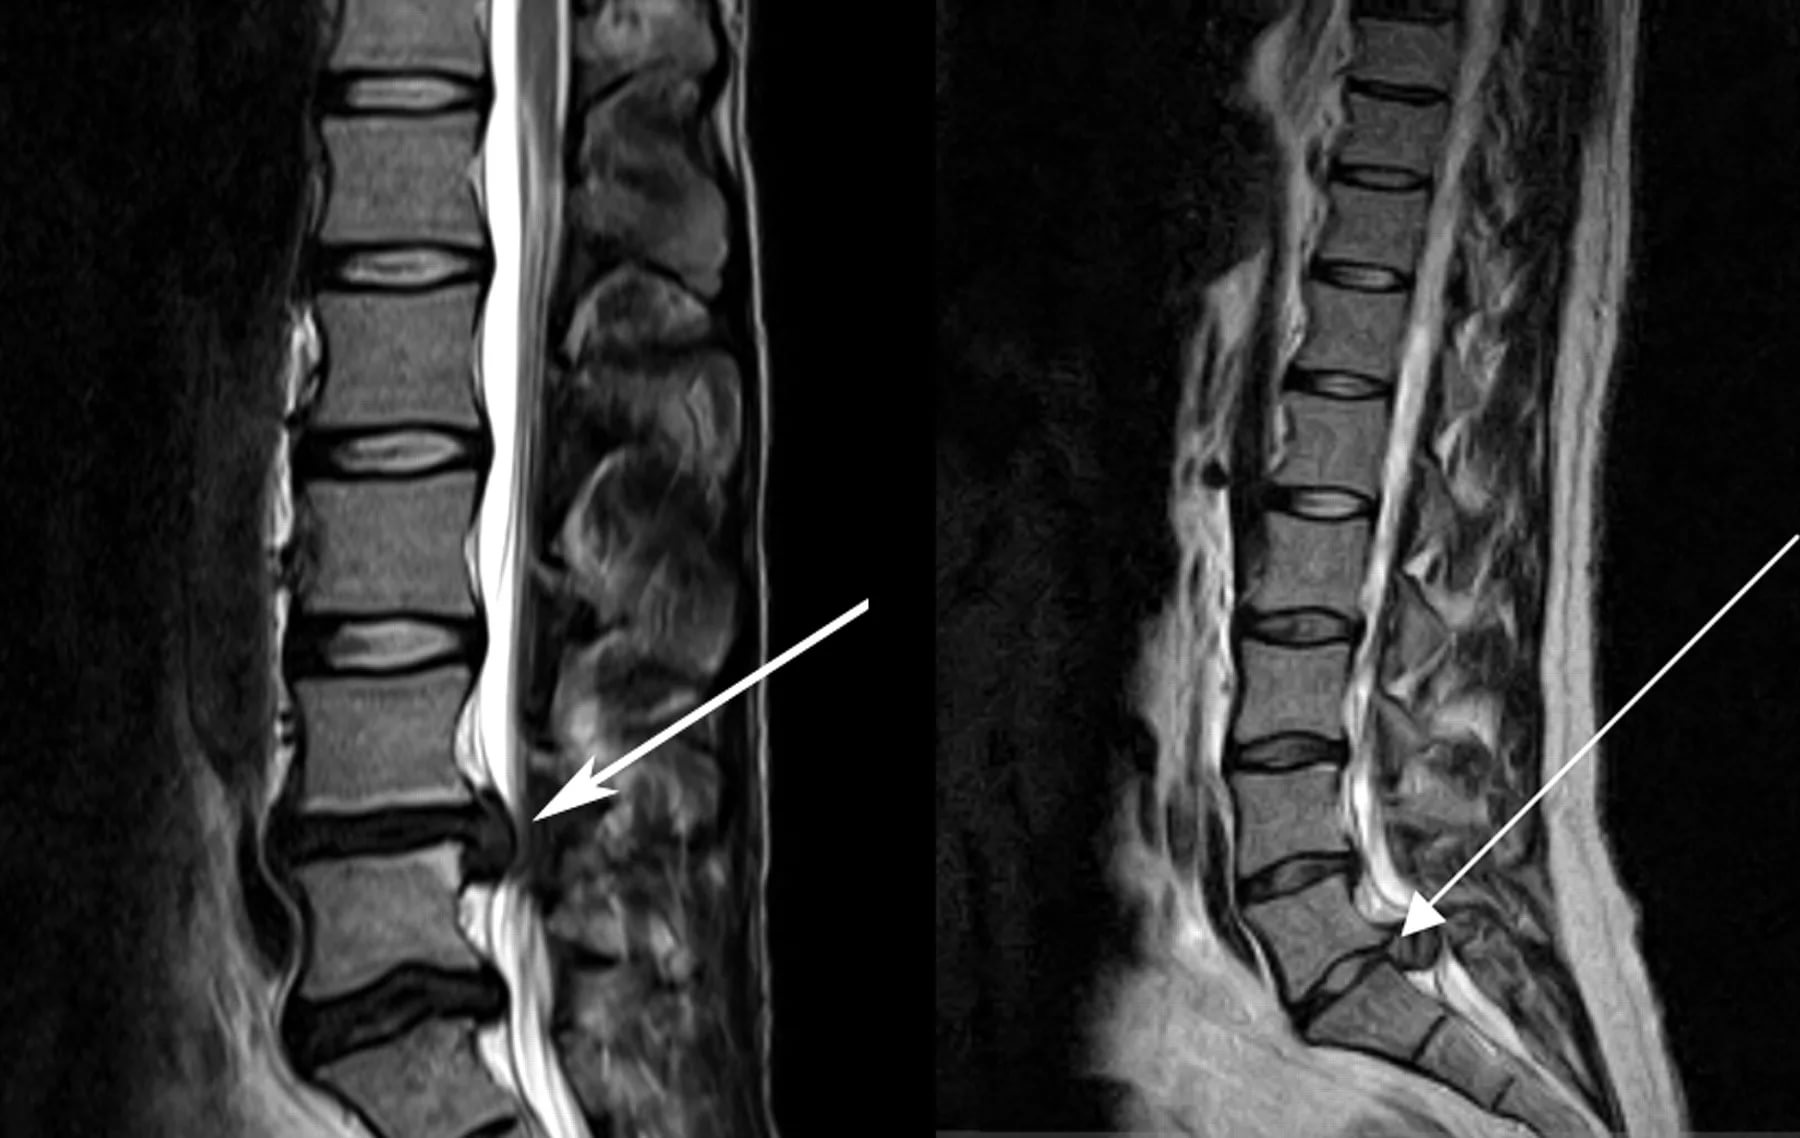

- Миело(томо)графия. Контрастное вещество вводится в субарахноидальное пространство для визуализации спинного мозга и оценки проходимости.

Для выявления различных новообразований в спинном мозге, позвоночнике и мягких тканях проводят магнитно-резонансную и компьютерную томографию.